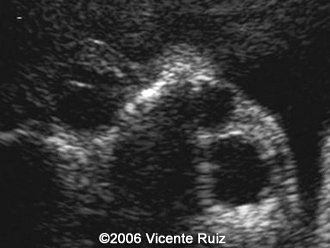

This is a case of dacryocystocele in a third  trimester fetus. Note the cystic mass between the right medial cantus and the nose.